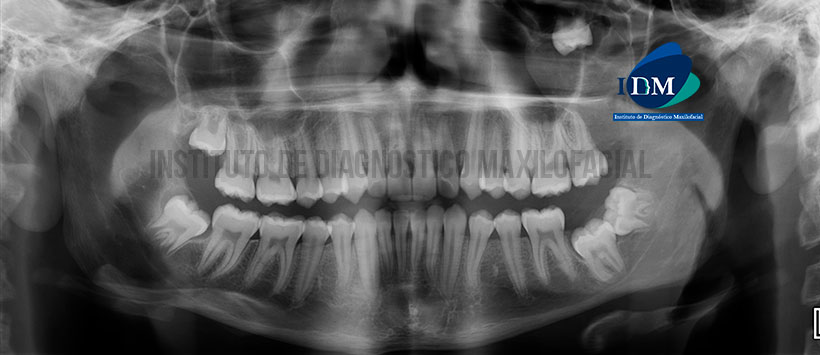

Paciente de 15 años de edad acude al Instituto de Diagnóstico Maxilofacial para evaluación imagenológica del maxilar superior

A la evaluación de la radiografía panorámica se visualiza un apiñamiento dentario del sector anterior, terceras molares en proceso de erupción y la pieza 37 retenida en posición vertical. Siendo lo ms resaltante la imagen radiopaca proyectada en seno maxilar izquierdo, próximo a la pared posterior del seno y tuberosidad del maxilar, de limites definidos, bordes corticalisados y aparentemente asociado a la pieza 28. (Figura 1)